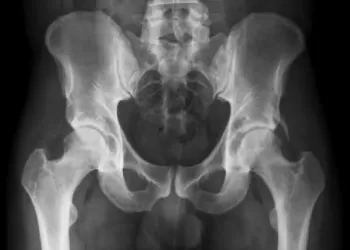

Doğuştan Gelen Hastalıklar